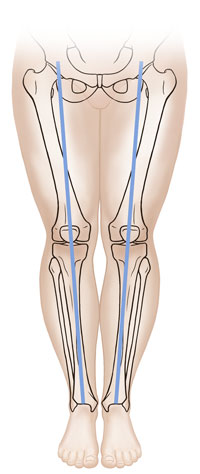

If your child’s legs curve outward, they have bowlegs. If your child’s knees come together and the lower legs point outward, they have knock knees. Often, a child will start out with bowlegs, the legs may straighten, then the child may become knock-kneed. Your healthcare provider will examine your child’s legs and may X-ray them to make sure there isn’t a structural problem.

| Normal. |